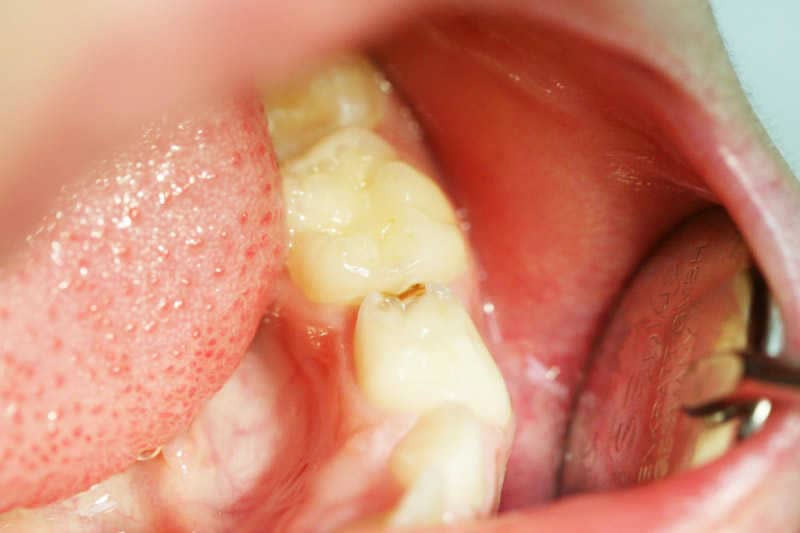

A bal alsó tejfog distalis és rágófelszíni szuvasodása